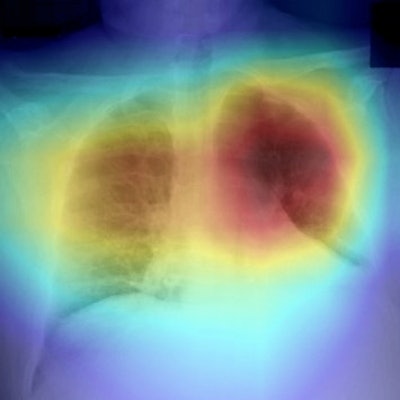

As the pandemic spread, AI developers quickly adapted algorithms designed to detect pneumonia and retooled them to recognize signs of COVID-19. One of the first was described by researchers from the University of California, San Diego, who showed in a March 20 paper that their algorithm was able to predict and localize COVID-related pneumonia in a small group of patients.

The open-source nature of AI development -- with developers working with common bits of computer code -- helped accelerate the rollout of new AI algorithms. A Canadian group was able to develop an algorithm called COVID-Net using two open-source datasets with nearly 6,000 chest x-rays. While they acknowledged that the algorithm did have some drawbacks, they posted the source code to the internet so others could pick up on their work.

And true enough, as 2020 wore on it appeared that the AI models were only getting better. A major help was the fact that developers soon were able to use actual COVID-19 cases for development and training, rather than repurposed pneumonia cases.

In September, researchers from Wisconsin unveiled their work on an AI algorithm developed specifically to address x-ray's shortcomings for COVID-19. They felt that part of the problem could be that many radiologists were seeing the disease for the first time, so they built a deep neural network called CV19-Net that generated heatmaps of possible SARS-CoV-2-related infection in the lungs. Its performance was comparable to or better than that of radiologists, they found.